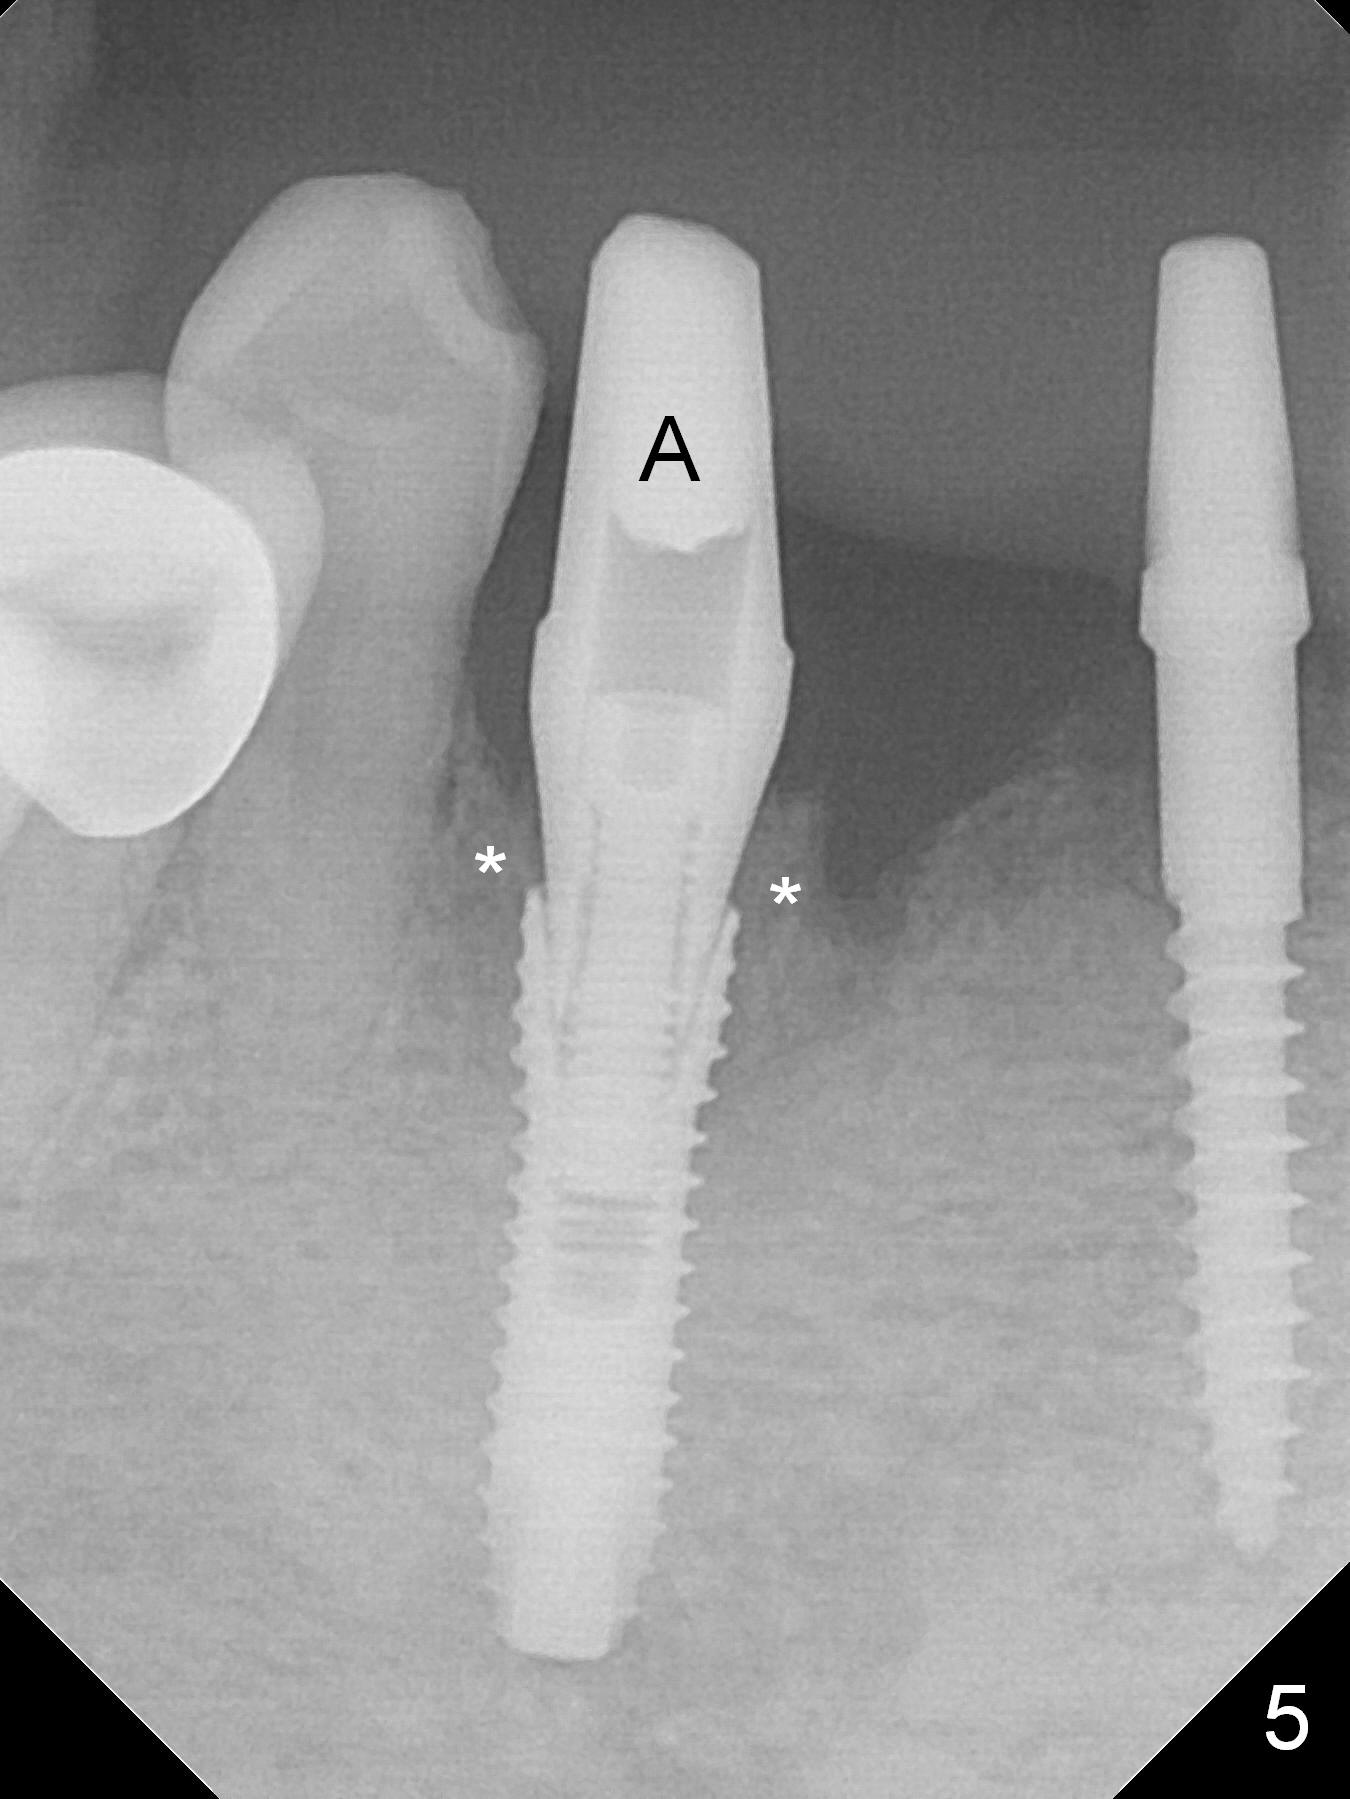

There is severe buccal gingival recession at #27 (Fig.1 arrow), as compared to that at #22. After removing the bridge and extraction of #27 (Fig.2 with severe loss of the buccal plate), a 3x18 mm drill is used to finish osteotomy (Fig.3). A 3.8x13 mm UF implant (Fig.3 green line) will be placed with 9 mm in the apparently solid, native (new) bone (blue line), while the coronal 5 mm will be occupied by the 5 mm cuff of a cemented abutment (pink line). The white dashed line is the gingival margin. The osteotomy is initiated as lingual as possible so that there will be at least 2 mm buccal gap when the narrow implant is placed. In spite of effort and precaution (guided surgery could control the trajetory), the coronal end of the implant tilts buccally so that a 4.5 mm 15 ° A 4 mm angled abutment is placed slightly subgingival (except buccal; Fig.5 A).

The mesial defect at #27 appears to have been repaired 8 months postop (Fig.8,9 *); there is no bone loss at 1-piece implant sites. The gingival recession seems to remain the same before and after removal of the provisional FPD (Fig.10,11). The bulging abutment at the cervix is less prominent when a straight abutment is used and prepared (Fig.12, 4.5x5.5(5) mm). There is no bone loss at #23, 25 and 27 sites 2.5 years post cementation (Fig.12-15), although the trajectory of the implants could be improved by using surgical guide (Fig.16-18).